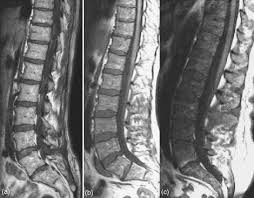

The Use Of Whole Body Mri In Multiple Myeloma Rcp Journals

The Use Of Whole Body Mri In Multiple Myeloma Rcp Journals from www.rcpjournals.org

Multiple myeloma is a cancer of plasma cells, which are white blood cells found mainly in the bone marrow. Find more information on clinical trials that are open for enrollment at mount sinai's center for excellence for multiple myeloma. Multiple myeloma (mm), also known as plasma cell myeloma and simply myeloma, is a cancer of plasma cells, a type of white blood cell that normally produces antibodies. Treatment response, detection of relapse. Related online courses on physioplus. 16,000 new cases and 11,000 deaths. Changing the treatment landscape for hematologic malignancies learn more. In multiple myeloma, when the cancer protein level is up, the normal antibody levels are down. If you still can't find it, please let us know so we can add it!. Tell the radiologist or the radiology technician about your diagnosis before receiving dye injection into. It accounts for approximately 10% of all. Other tests include blood monoclonal immunoglobulin and radiology tests to determine the extent of bone lesions. Spotlight revised international staging system for multiple myeloma: